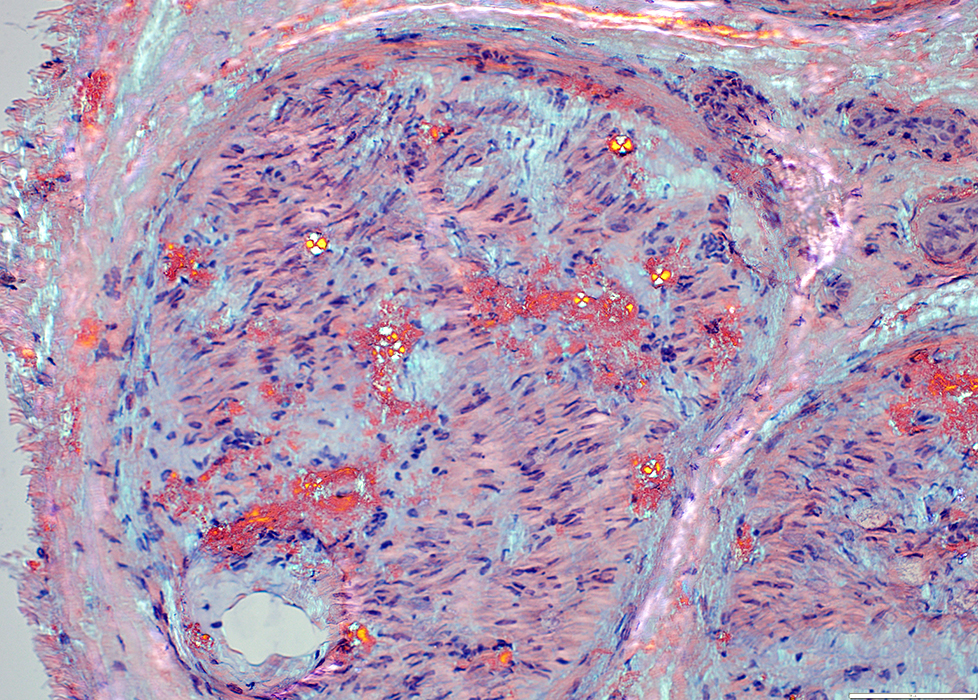

Amyloid: Multifocal Deposition

Locations

Endoneurial connective tissue

Around endoneurial microvessels

Perineurium

Epineurial connective tissue

Epineurial vessel walls

Amyloid: Congo red birefringence

Maltese cross pattern in some areas